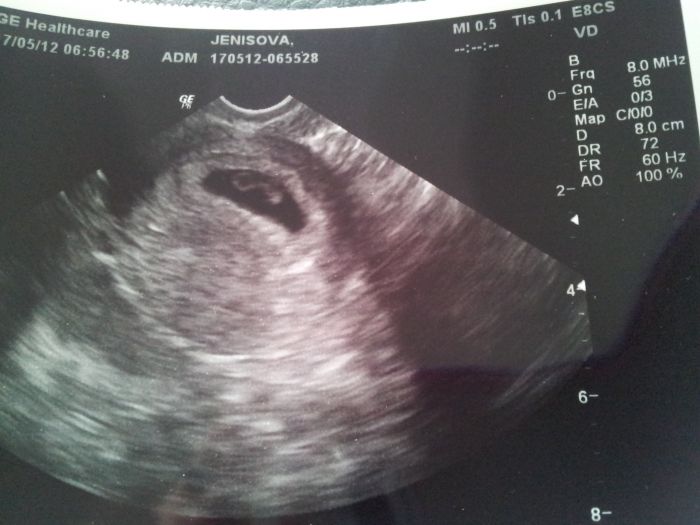

Pridavam i fotecku. Tak se taky pochlubte miminkama a hak vam rostou pupiky.

Ahojky děvčata, krásné termíny a pěkná fotečka marselinka. jsem 10tt+2 termín úžasnej 24.12.2012 no prostě ježíšek.

Ahoj holky, jé takovej mimísek, my už jsme o dost větší, je to mazec jak mrňousek roste. Já už na screeningu byla ale ještě nevím výsledky ty se dozvím až v úterý, tak snad bude vše v pořádku.

jinak je to mé druhé těhu, ale to první nevydařené, tak doufám,že nám teď bude štěstíčko přát a vše dopadne dobře. Jdu na screening až 20.6, takže jsem už teď celá nervózní, jak to vše dopadne. Zatím nemám ani těhotenskou průkazku, až za 14dní. No už chci mít další fotečku, kde je cvrček trošku zřetelnější, na ten malý flíček po prvním ult v 6tt se kouká tak zvláštně